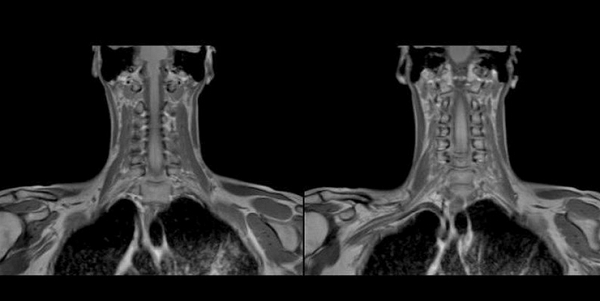

Снимки МРТ мягких тканей шеи

Проведение магнитнорезонансной томографии с использованием различных режимов повышает информативность исследования рыхлых элементов. Изучение особенностей кровоснабжения зоны интереса и диагностика новообразований требуют применения контрастного раствора. В качестве «окрашивающего» препарата используют хелаты гадолиния.

Мягкие ткани шеи на МРТ